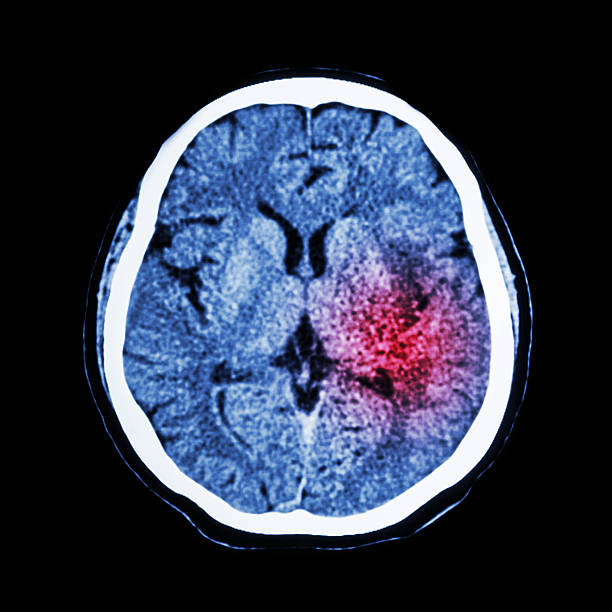

뇌출혈은 뇌안에 있는 혈관에서 출혈이 발생하여 뇌조직이 손상을 입는 질환이며, 중증의 뇌혈관질환 중 하나입니다. 일반적으로 고혈압, 동맥류, 혈관 기형, 혈전 등의 이유로 혈관이 파열하거나 뚫리면서 발생합니다.

고혈압은 뇌출혈을 일으키는 가장 일반적인 원인 중 하나입니다. 고혈압은 혈관벽을 약화시켜 혈관이 파열하기 쉽게 만들기 때문입니다. 또한, 혈관에 생긴 약간의 이상증상이나 동맥류, 혈관 기형 등도 뇌출혈의 원인이 될 수 있습니다.